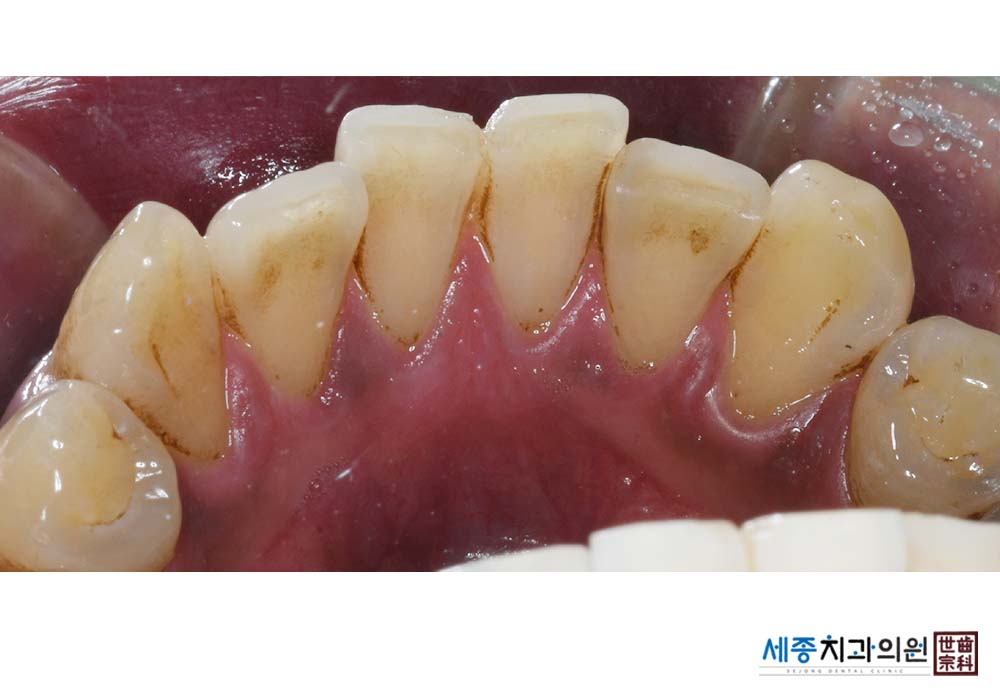

[스케일링] 치주질환 예방 스케일링

치료전 : 2023-02-20

가글마취&저주파 스켈러를 사용한 스케일링